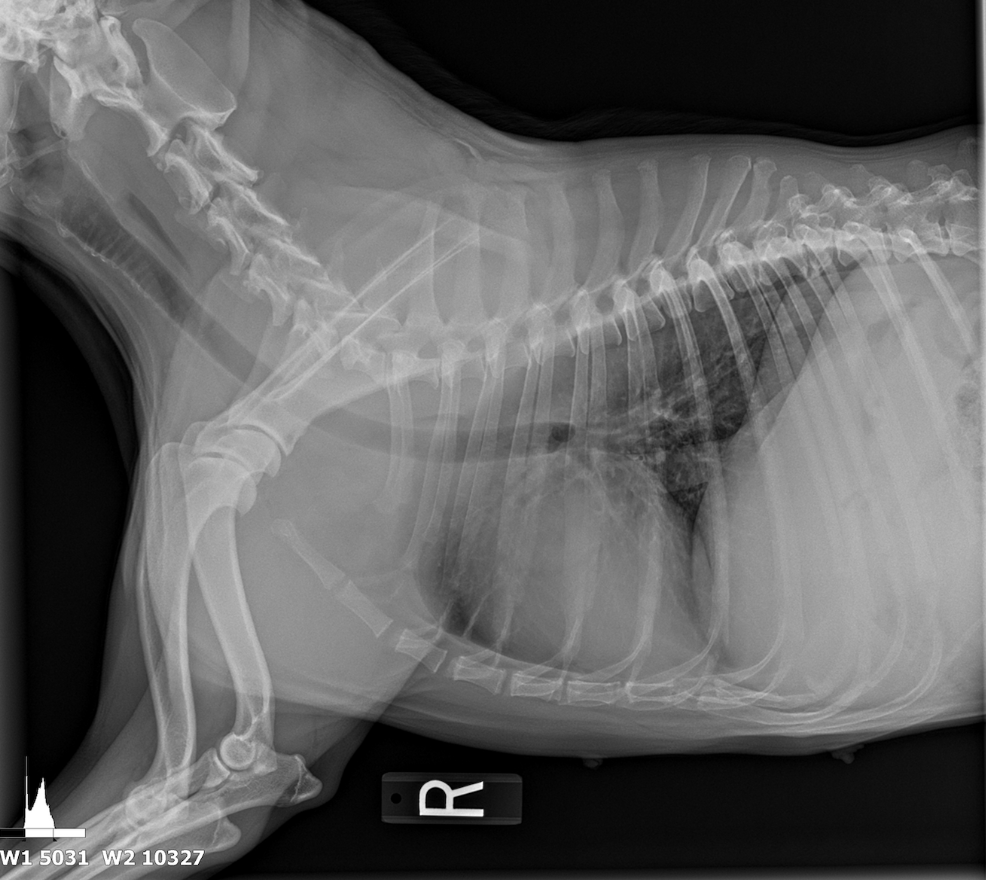

The patient was referred from another veterinary clinic for advanced imaging following the identification of a suspected abdominal mass on radiographs. Ultrasonographic evaluation revealed a splenic mass consistent with an abscess, from which purulent fluid was aspirated and drained. A splenectomy was scheduled for later the same day.

At presentation, the patient was lethargic and febrile. Physical examination and diagnostic testing revealed multiple abnormalities. The complete blood count (CBC) demonstrated a non-regenerative anemia (hematocrit 25%) and marked leukocytosis characterized by neutrophilia (neutrophil count: 21,000/µL). Serum chemistry showed elevated alkaline phosphatase (ALP) and increased globulin concentrations. A 4DX test returned negative results, and a coccidioidomycosis titer was pending at the time of reporting.

The spleen revealed an expansive parenchymal mass that measured 10+ cm without evidence of cavitation. Hyperechoic fat was noted around the spleen. This is consistent with inflammation.